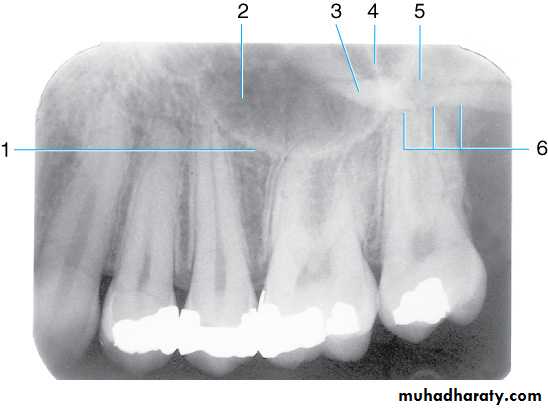

Radiograph of maxillary premolar area. This radiograph shows the (1) border (floor) of maxillary sinus, (2) maxillary sinus, (3) zygomatic process of maxilla, (4) septum in maxillary sinus dividing the sinus into two compartments, (5) zygoma, and (6) inferior border of the zygomatic arch

Radiographic Anatomy Basics

Drawing of maxillary molar area. Illustrated in the drawing are the (1) border (floor) of maxillary sinus, (2) maxillary sinus, (3) zygomatic process of maxilla, (4) zygoma, (5) septum in maxillary sinus, (6) lower border of zygomatic arch, (7) hamulus (hamular process), (8) maxillary tuberosity, and (9) coronoid process (mandible)